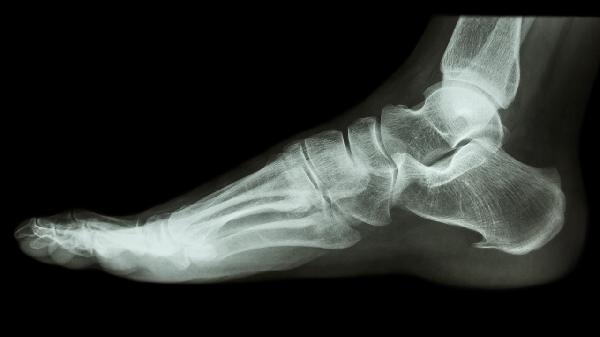

椎间盘突出的X线表现有哪些

椎间盘突出的X线表现主要有椎间隙变窄、椎体边缘骨质增生、脊柱生理曲度改变、椎间孔狭窄、椎体滑脱等。X线检查虽不能直接显示椎间盘组织,但可通过间接征象辅助诊断。

椎间盘退变或突出时,髓核水分减少导致椎间隙高度降低。X线侧位片显示相邻椎体间距离缩短,多见于腰4-5和腰5-骶1节段。长期椎间隙狭窄可能加速相邻椎体终板硬化。

椎间盘突出后稳定性下降,机体通过骨赘形成代偿性加固。X线可见椎体前缘或后缘唇样突起,严重者形成骨桥。骨质增生可能压迫神经根或脊髓,需结合CT或MRI进一步评估。

椎间盘突出可导致脊柱侧弯或生理前凸减小。X线正位片显示脊柱侧凸,侧位片可见腰椎前凸角度减小甚至反弓。这种代偿性姿势改变是为减轻神经根受压产生的疼痛。

斜位X线片可观察椎间孔形态,椎间盘向后外侧突出时,相应节段椎间孔横径缩小。骨性椎间孔狭窄常合并椎间盘突出,两者共同导致神经根卡压症状。

严重椎间盘退变可能引发椎体稳定性丧失,X线侧位过屈过伸位可见椎体前后移位。退行性滑脱多见于腰4椎体,动态摄片有助于判断滑脱是否具有活动性。